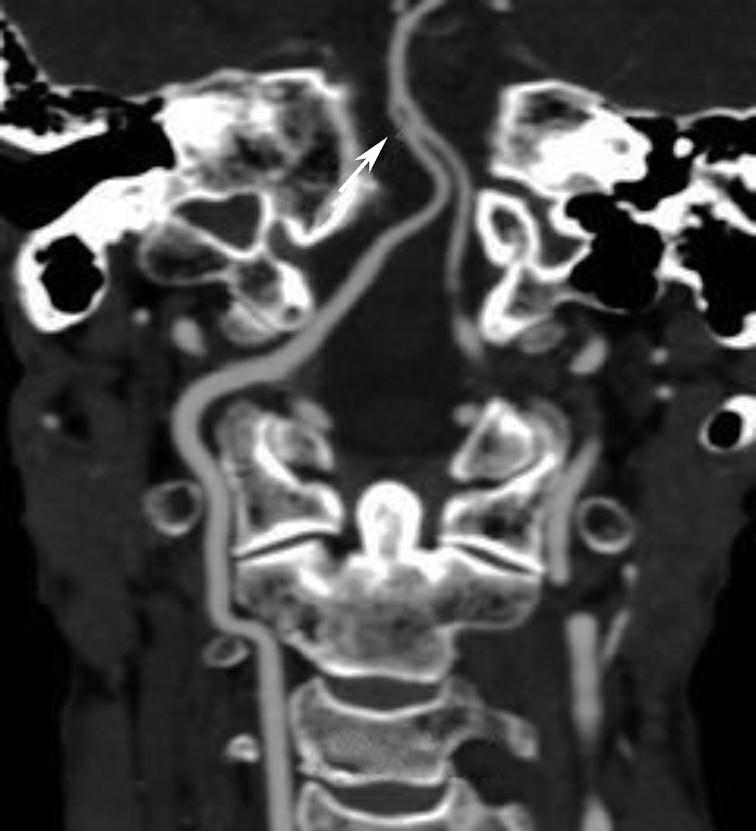

破裂孔、卵圆孔、棘孔及斜坡等均为重要的解剖结构,临床常见疾病如鼻咽癌常侵犯上述结构(图1-2-3)。颈静脉孔区较常见的肿瘤为颈静脉球瘤,常伴有颈静脉孔及其邻近骨质的破坏(图1-2-4)。

图1-2-3 鼻咽癌颅底骨质破坏

A.横断面;B.横断面(骨窗)

骨窗示左侧岩尖、斜坡、左侧蝶骨大翼骨质破坏、受侵(白箭),肿瘤经破裂孔侵入颅内(黑箭头)